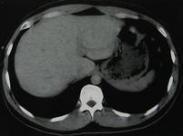

• 腹膜后血腫

628健康網為您分享有關腹膜后血腫的癥狀,腹膜后血腫的治療方法,腹膜后血腫的預防知識,腹膜后血腫的癥狀圖片,腹膜后血腫...